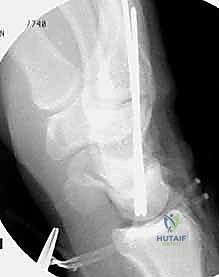

TECH FIG 6 • A. K-wire placed in triquetrum at a 45-degree angle.

TECH FIG 6 • B. K-wire advanced into lunate.

TECH FIG 6 • C. Second K-wire placed in lunotriquetral joint.

- K-Wire Placement: Once reduced, we need to temporarily stabilize the joint.

- First K-wire: Insert a 0.045-inch or 0.062-inch smooth K-wire into the triquetrum at approximately a 45-degree angle, aiming towards the lunate. Advance this wire across the lunotriquetral joint and into the lunate. Ensure good purchase in both bones.

- Second K-wire: Place a second K-wire across the lunotriquetral joint, ideally starting from the lunate and crossing into the triquetrum, or vice-versa, to provide rotational stability. This creates a more rigid construct.

- Fluoroscopic Confirmation: Use intraoperative fluoroscopy to confirm anatomical reduction and optimal K-wire placement. Check both AP and lateral views. Ensure the wires are not impinging on articular surfaces or neurovascular structures.